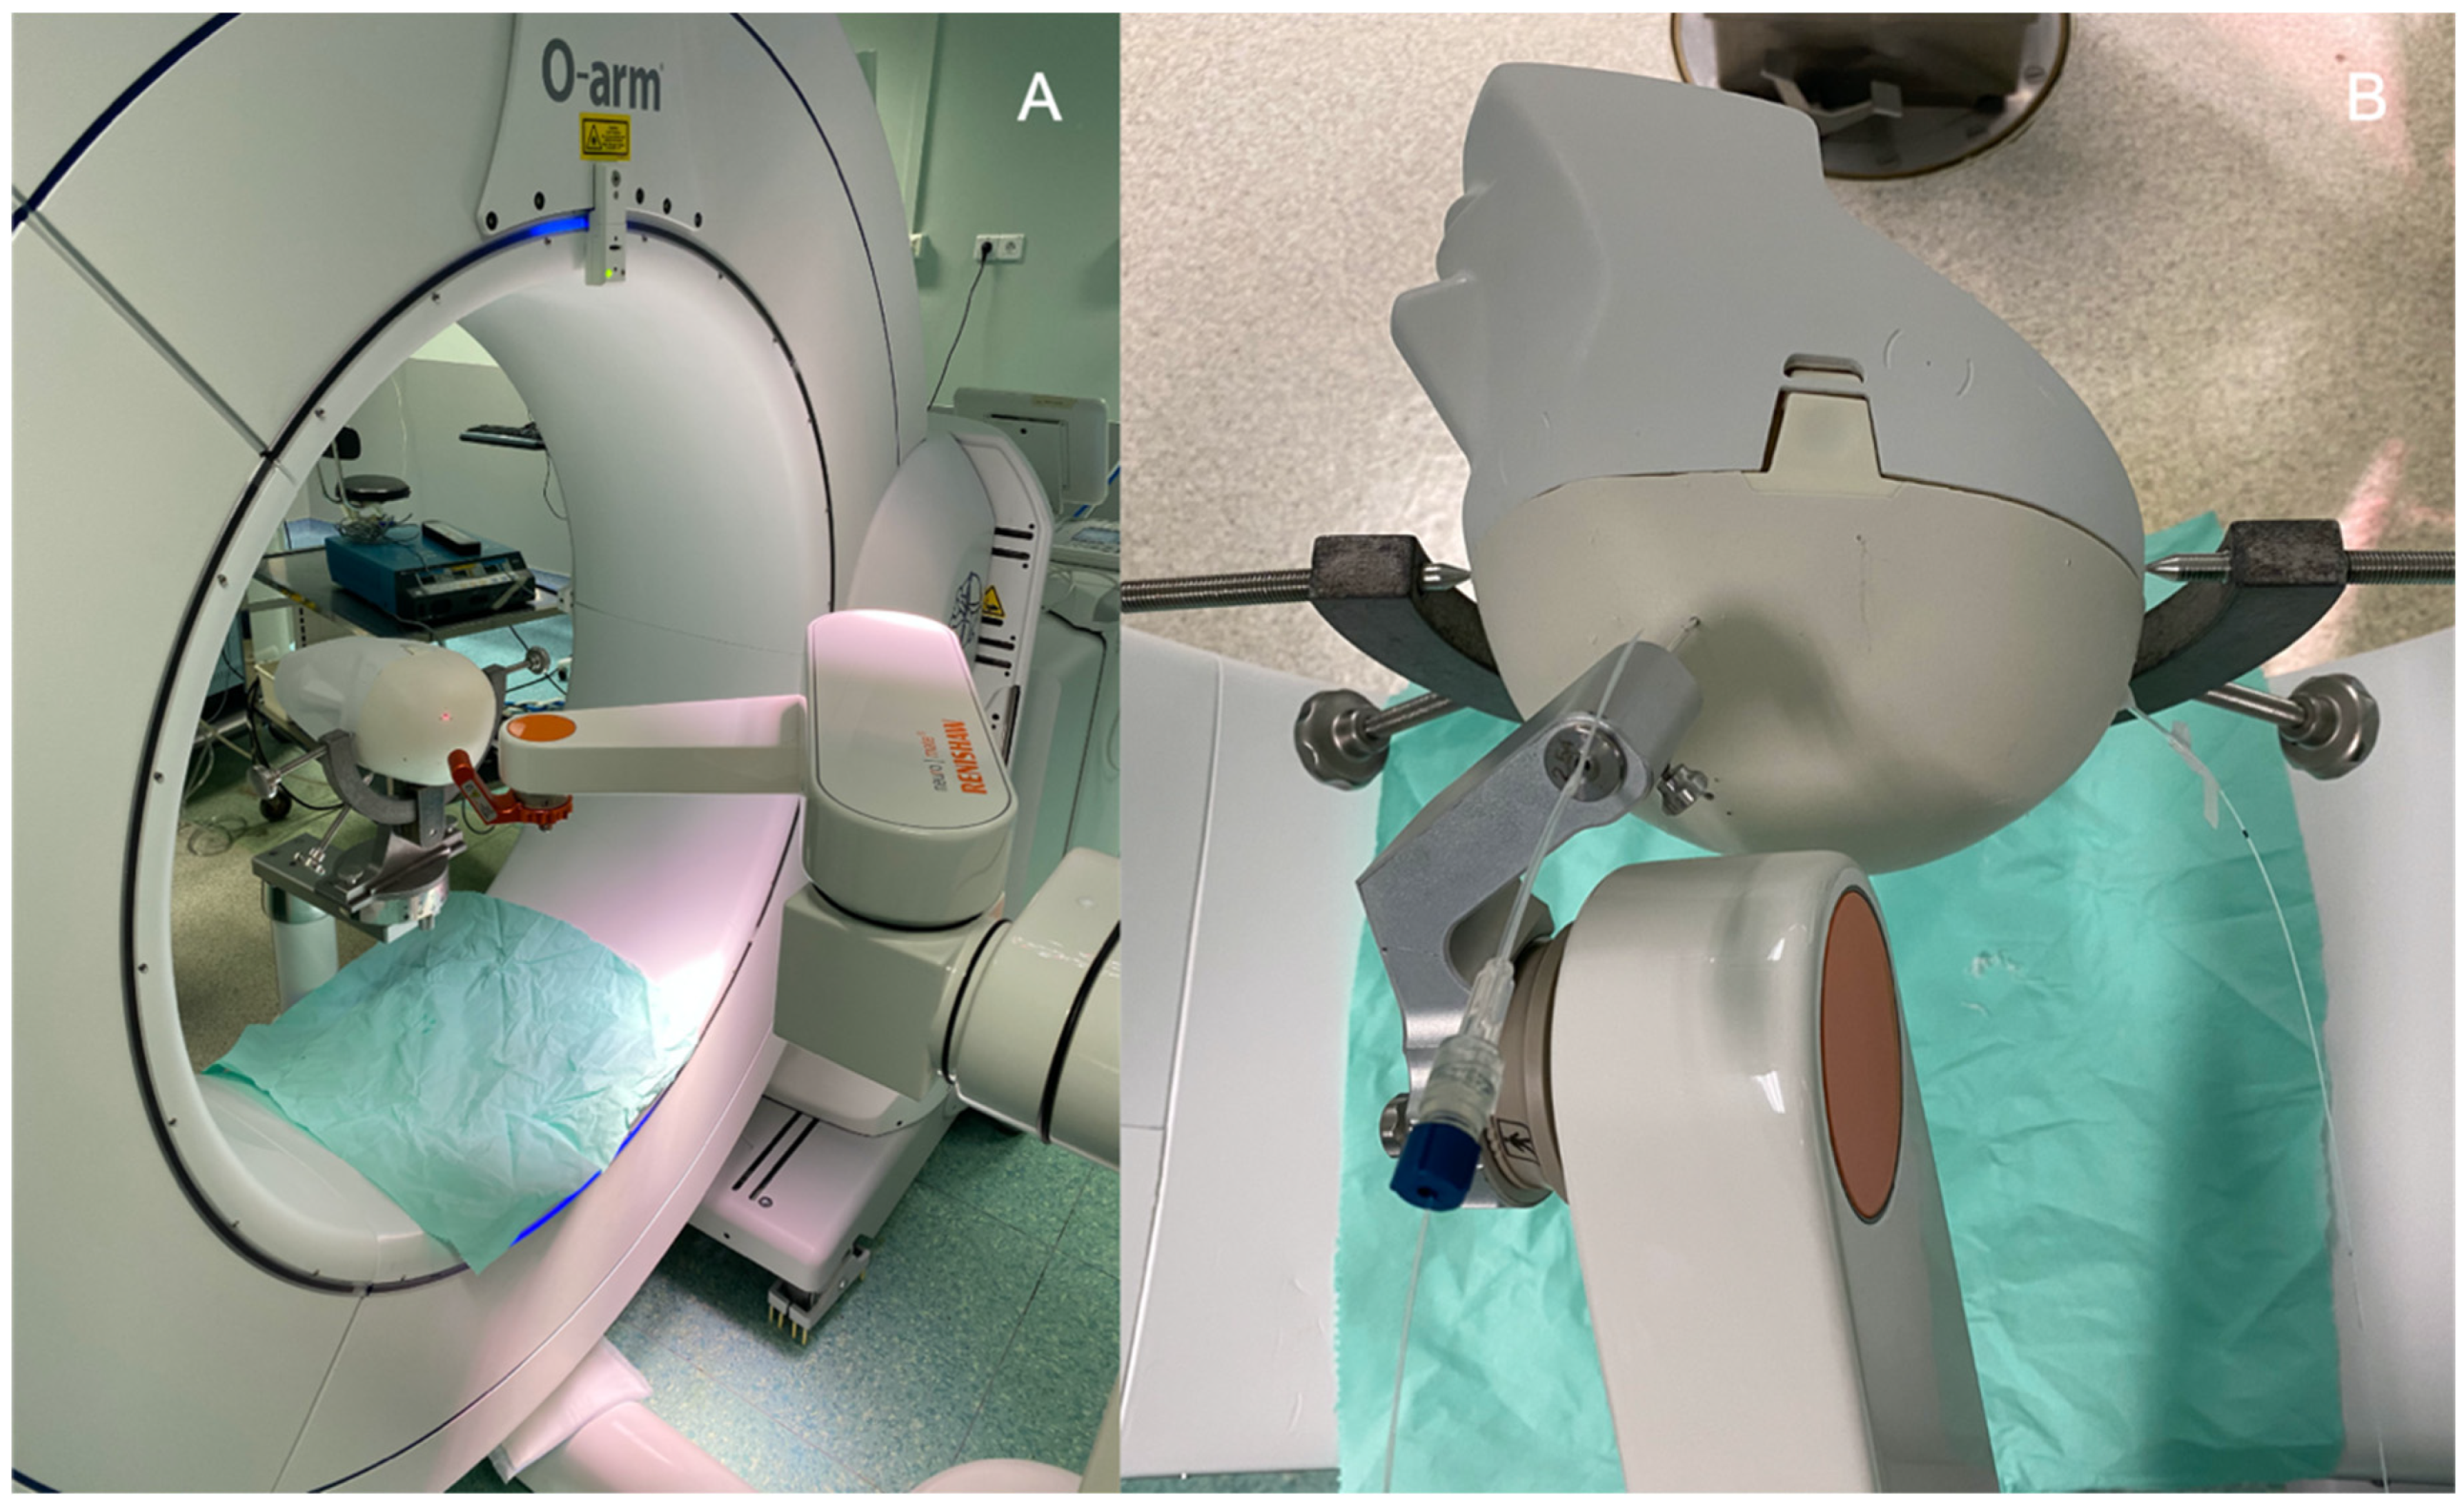

2.2. Surgical Procedure